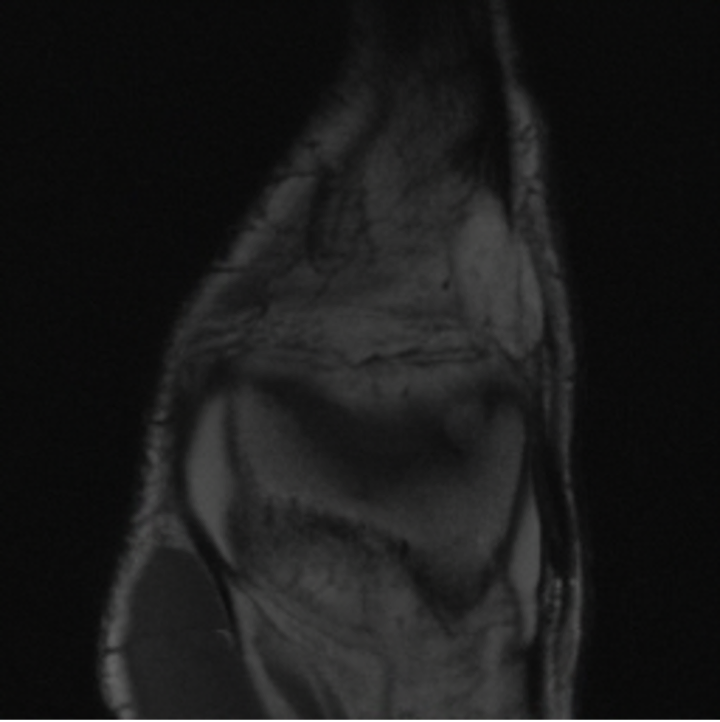

5.3 Out-of-Domain Generalisation

One way to test the generalization capability of the trained X-Diffusion is to test it on a completely different domain from an MRI dataset not seen during training. We report the single-slice results on NYU fastMRI [37, 82], a knee MRI dataset, using the X-Diffusion trained on the BRATS brain MRIs. The results are shown in Figure 9 and Table 2. It shows how successfully X-Diffusion is able to generate knee MRIs from a single image, despite not seeing knees at all in training. To qualitatively assess how realistic our generated 3D volumes were (produced from a single slice), we gave 20 generated examples alongside their real MRI counterparts to an expert orthopaedic surgeon. He was then asked to identify the real example from a given pair. The surgeon identified with certainty only 10 real knee MRIs out of 17, while could not decide on the remaining 3 of the 20 MRI pairs. This further validates the generated out-of-domain MRIs.